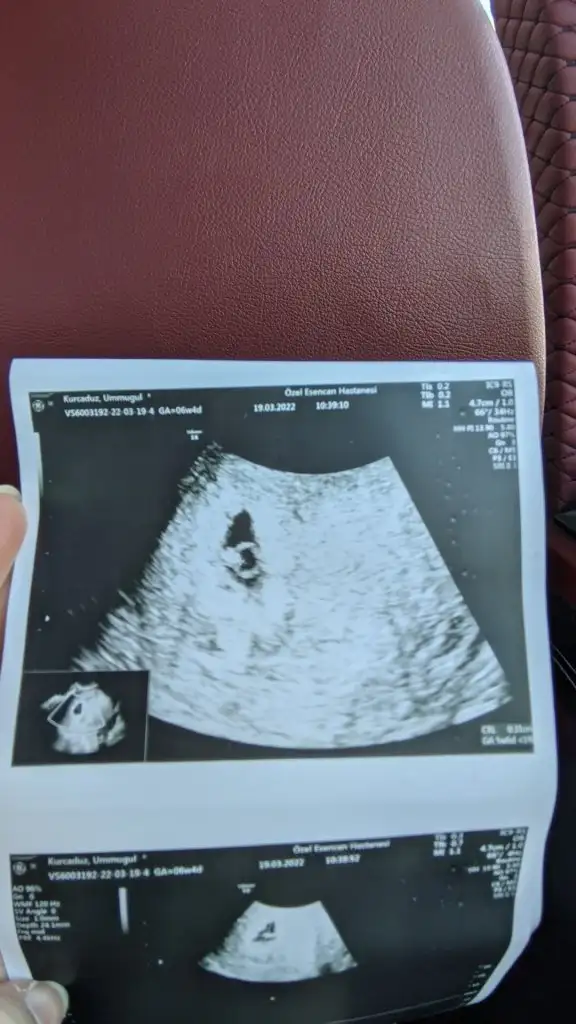

Merhaba banada tahminde bulunurmusun karından ve burda 7 ve 12 haftalıkSelam Kızlarbir çok kişi gruplardan beni bilir. Yine yetiştim imdatlara

kuzum kız gibi duruyorMerhaba banada tahminde bulunurmusun karından ve burda 7 ve 12 haftalık

kuzum karından mı?Banada bakarmisiniz lütfenn

kuzum bence kızBanada bakarmisiniz lütfenn

Allah hayırlısını sağlıklısını versin inşallah.. Teşekkür ederim netleşince yazarımkuzum kız gibi duruyor